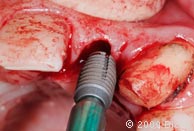

18. Введение имплантата 4.5х8.0мм в лунку с помощью специального инструмента.

19. Введение имплантата 4.5х8.0мм в лунку с помощью специального инструмента.